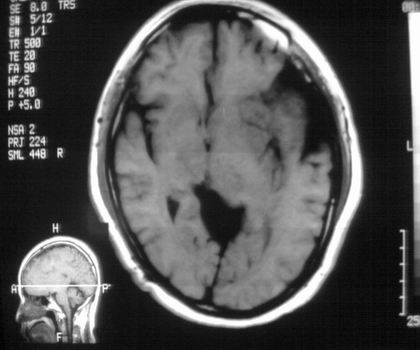

以下是引用影像孺子牛在2008-4-29 21:20:00的发言:[br]首先病变定位在脑外,根据ct密度及mri信号特征考虑慢性硬膜下血肿不连续环形钙化。

以下是引用周战梅在2008-4-29 23:12:00的发言:[br]脑外病变,蛛网膜下腔增宽,囊壁点状、环形钙化,增强扫描呈不均匀环状强化,考虑为囊性脑膜瘤可能性大,慢性脓肿、血肿机化、胆脂瘤不能除外。